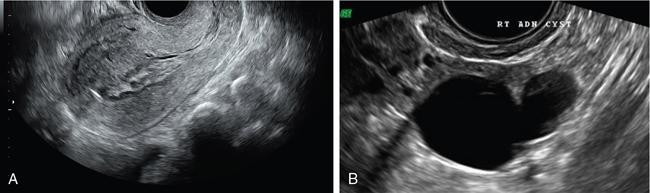

John De Lindsay, Subhashree C SALPINGITIS Salpingitis refers to the diffuse inflammation of the fallopian tubes and can be unilateral or bilateral. It is the most common early form of PID. Salpingitis has the highest risk of infertility and ectopic pregnancies. Coexisting endometritis can be seen in up to 70%–90% of nonobstetric patients. The clinical presentation in salpingitis can be variable, from being asymptomatic to severe pelvic discomfort and tenderness. Poor correlation is often noted between the degree of symptoms and the extent of tubal inflammation. In salpingitis, the fallopian tubes become hyperemic and swollen due to inflammation. With suppurative salpingitis, the lumen of the tube distends with pus and spills over into the peritoneal cavity, coating the serosa of the adjacent uterus and ovary. US maybe used as the first-line imaging modality for evaluating suspected salpingitis. Subtle abnormalities such as fallopian tubal tenderness with tortuosity, increased wall vascularity and tubal thickening of more than 5 mm may be considered pointers towards salpingitis. Salpingitis may be considered on CT when the fallopian tube thickening is more than 5 mm in axial dimension with enhancing walls (Fig. 11.17.1.1). Adjacent peritubal free fluid or cul-de-sac fluid may be other indicators. Fallopian tube thickening is the most specific sign to arrive at a diagnosis of salpingitis (Fig. 11.17.1.1). Chronic salpingitis may present as diffuse tubal irregularity with narrowing or complete obliteration of the tubes. Salpingitis isthmica nodosa is a benign inflammatory process causing nodular scarring of the fallopian tubes. At hysterosalpingography, tubal irregularity and subcentimetric protrusions from the isthmic portion of the tube are seen. PELVIC INFLAMMATORY DISEASE Pelvic infection is one of the most frequent cause of pelvic pain in females. Diagnosis of pelvic inflammatory disease (PID) can be challenging because it mimics other abdominal and pelvic processes. Pelvic ultrasonography is the first line investigation of choice. Multimodality imaging with CT and MRI are required for making a definitive diagnosis and for assessing the extent of disease and complications. PID is a spectrum of disease where microorganisms cause an inflammatory continuum ascending from the lower genital tract to infect the uterus, fallopian tubes, ovaries and may extend to the peritoneal cavity. The infection begins with cervicitis and progresses to endometritis, salpingitis, pyosalpinx, tubo-ovarian complex and ultimately tubo-ovarian abscess (TOA) (Fig. 11.17.2.1). One-third to one-half of cases are due to chlamydia trachomatis or Neisseria gonorrhoeae. However, PID is most commonly (30%–40%) a polymicrobial infection and substantial proportion of cases are nongonococcal and nonchlamydial in origin. It may be due to vaginal flora, anaerobic gram-negative rods and Mycoplasma bacteria. Tuberculosis and actinomycosis occur less frequently. Risk factors for PID include young age, multiple sexual partners, an increased frequency of coitus and the presence of intrauterine contraceptive device. Secondary infection of adnexa from gastrointestinal origin like appendicitis and diverticulitis is also common. Clinical diagnosis of acute PID often presents a challenge due to overlap of symptoms and signs with conditions like endometriosis, appendicitis and ectopic pregnancy. Symptoms: Pelvic pain is the most common symptom, although may be absent or mild in some patients. Mucopurulent vaginal discharge and fever are the other usual symptoms. Signs: Per vaginal examination reveals cervical motion tenderness, uterine and adnexal tenderness. Chronic PID symptoms: Patients may be asymptomatic. They can present with chronic pelvic pain, low back ache, dyspareunia, abnormal vaginal bleeding and vaginal discharge. WBCs on saline microscopy of vaginal secretions, elevated ESR, CRP and leucocytosis. A delay in treatment of PID causes significant reproductive and gynaecologic morbidity, such as infertility, increased risk of ectopic pregnancy, chronic pelvic pain and recurrent infection. Hence there is need for proper and adequate treatment of this condition. Most patients can be treated as out-patients with broad spectrum antibiotics. Hospitalisation is required in severe cases like TOA (Fig. 11.17.2.2). Inflammation of uterine cervix. May be infectious or noninfectious. Infectious cervicitis represents early presentation of PID. USG shows an enlarged cervix and hyperaemic cervical canal. CT and MRI show an enhancing endocervical canal. Cysts can be seen lining the endocervical canal. Cervical stroma is usually intact. Differentiation from cervical malignancy is made by lack of enhancing solid components in the abnormal cervix. Inflammation of the endometrial lining of uterus. Usually occurs during pregnancy or postpartum state or gynaecologic instrumentation. USG imaging findings depend on stage of PID. In early or mild infection, the findings are nonspecific. Endometritis may not exhibit any sonographic findings. A fluid-filled endometrial cavity is suggestive of endometritis in the setting of fever, vaginal discharge and uterine tenderness on physical examination. Intrauterine fluid is a nonspecific finding. Gas in the endometrial cavity will appear as foci of increased echogenicity with posterior dirty shadowing. Presence of gas increases the possibility of infection, though gas in the endometrial cavity can be present postpartum and postinstrumentation. Fluid in cul-de-sac is again a nonspecific finding. Internal echoes within the fluid could suggest infection (or haemorrhage) (Fig. 11.17.2.3A).